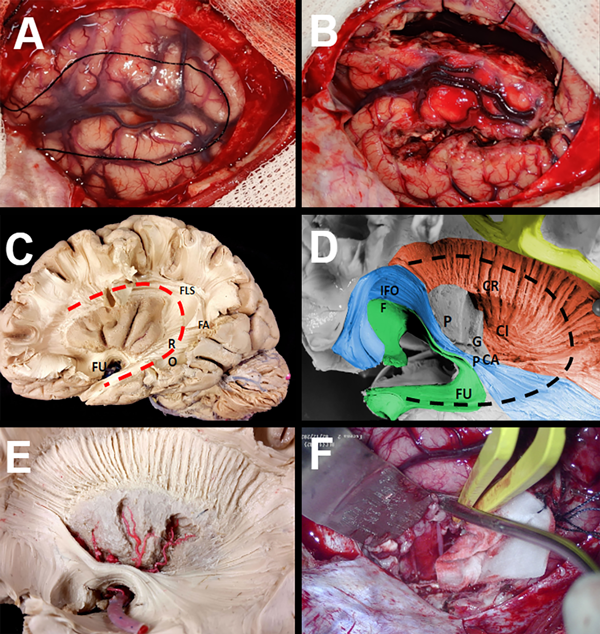

Figura 1. Fotografías y disecciones intraoperatorias que ilustran la técnica de HPI modificada. A: Exposición cortical lateral en el lado izquierdo que muestra la fisura de Silvio y la corteza temporal, parietal y frontal. B: Se realiza una incisión cortical paralela al ventrículo. C-D Luego se utilizó una ventana temporal transopercular, transcortical, para exponer el resto del ventrículo lateral, y a través de esta se realizó una resección por aspiración subpial del uncus y la amígdala. E-F Ligadura de la ACM en la fisura de Silvio proximal.

Figura 2. Dibujo representativo, disecciones e imágenes intraoperatorias que ilustran la técnica de HPI modificada. Después de entrar en el ventrículo, el opérculo frontal y temporal junto con la ínsula y porciones del núcleo caudado, el tálamo y los ganglios basales, se separan y extraen justo lateralmente al plexo coroideo(C). Esto expone el sistema ventricular (D).

Para describir de manera más detallada la HPI modificada, se practica una incisión cortical inicial, realizada a lo largo del opérculo frontal paralela al ventrículo y profundizada hasta que se ingresa al asta frontal del ventrículo lateral (Fig. 1 A-B). La apertura ventricular continúa posteriormente hasta el atrio del ventrículo lateral y se continúa posteriormente hasta la extensión anterior del asta temporal (Fig. 1 A-D). En este punto, se identifican, coagulan y ligan las ramas proximales de la arteria cerebral media, distales a los vasos perforantes profundos (Fig. 1 E-F). Usando el plexo coroideo como nuestro límite medial, el opérculo frontal y temporal junto con la ínsula y porciones del núcleo caudado, el tálamo y los ganglios basales se separan y resecan, exponiendo de esta manera el sistema ventricular (Fig. 2 A-D). Desde el asta frontal del ventrículo lateral, se realiza una callosotomía trans-ventricular, desconectando el cuerpo calloso hasta identificar la aracnoides sobre las arterias pericallosas (Fig. 3 A-D). Esta callosotomía transventricular se extiende luego desde el asta frontal hasta la desconexión occipital mesial. Posteriormente, una vez alrededor del esplenio, se extiende la incisión medial anteriormente hasta alcanzar la fisura coroidea, desconectando la fimbria del hipocampo del fórnix (Fig. 3 E-F). Se realiza una desconexión frontal profunda incidiendo justo por delante de los ganglios basales en un plano coronal desde el aspecto anterior del cuerpo calloso hasta la aracnoides de la región orbitofrontal. La identificación del giro recto y el tracto olfatorio proporciona buenos puntos de referencia anatómicos al llegar a la etapa más profunda. Preservar la piamadre basal agrega seguridad a este paso. Finalmente se realiza una amigdalo-hipocampectomía selectiva donde se extirpa el uncus y la amígdala mediante aspiración subpial y se reseca el hipocampo anterior hasta llegar a la fisura coroidea (Fig. 3 E-F).